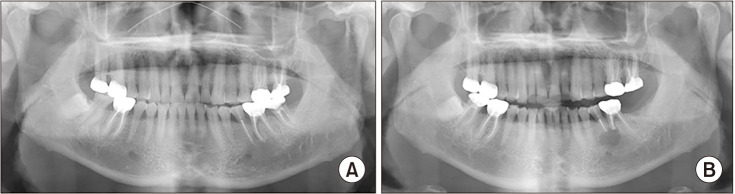

Results: A total of 147 teeth was included in this study. All the operated teeth underwent preoperative root canal treatment by an endodontic specialist. Apicoectomy was performed for 119 inflammatory cysts and 28 non-inflammatory cysts. Retrograde filling was performed on 22 teeth with inflammatory cysts and 3 teeth with non-inflammatory cysts. All teeth survived the 3.5-year follow-up (range, 1.0-9.1 years). However, 1 tooth with an inflammatory cyst developed complications 1 year after surgery that required re-endodontic treatment.